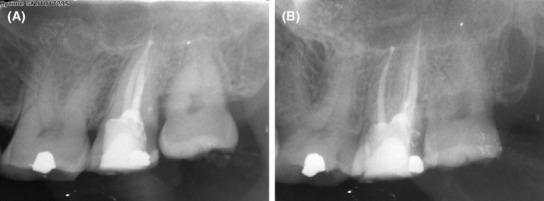

This case report describes the unusual location of the distobuccal root canal in a maxillary second molar with root fusion. On access opening, three distinct root canal orifices, the mesiobuccal canal, palatal canal, and a third orifice closer to the palatal canal, were seen, giving an illusion of an additional palatal canal. An attempt was made to search for the distobuccal canal in its usual position, leading to the gouging of the pulp chamber floor. An intraoperative limited field of view cone-beam computed tomography (CBCT) revealed the root orifice adjacent to the palatal canal was the distobuccal canal. CBCT also revealed fusion of both the buccal and palatal roots in the root's coronal and middle third region, but they were not fused apically.

本病例报告描述了一例上颌第二磨牙牙根融合时远颊根管的异常位置。在开髓时,可见三个明显的根管口,即近颊根管、腭根管以及靠近腭根管的第三个根管口,给人一种额外腭根管的错觉。试图在其通常位置寻找远颊根管,导致髓室底被凿穿。术中有限视野锥形束计算机断层扫描(CBCT)显示,靠近腭根管的根管口是远颊根管。CBCT还显示颊根和腭根在牙根冠部和中部三分之一区域融合,但根尖未融合。